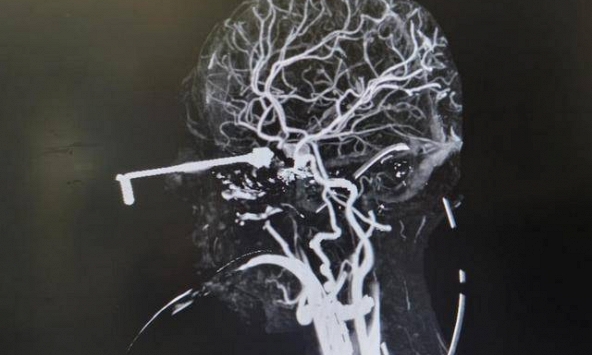

Bé 3 tuổi bị kim móc đâm xuyên não, bác sĩ nhấn mạnh “3 nguyên tắc sơ cứu” cha mẹ tuyệt đối phải nhớ